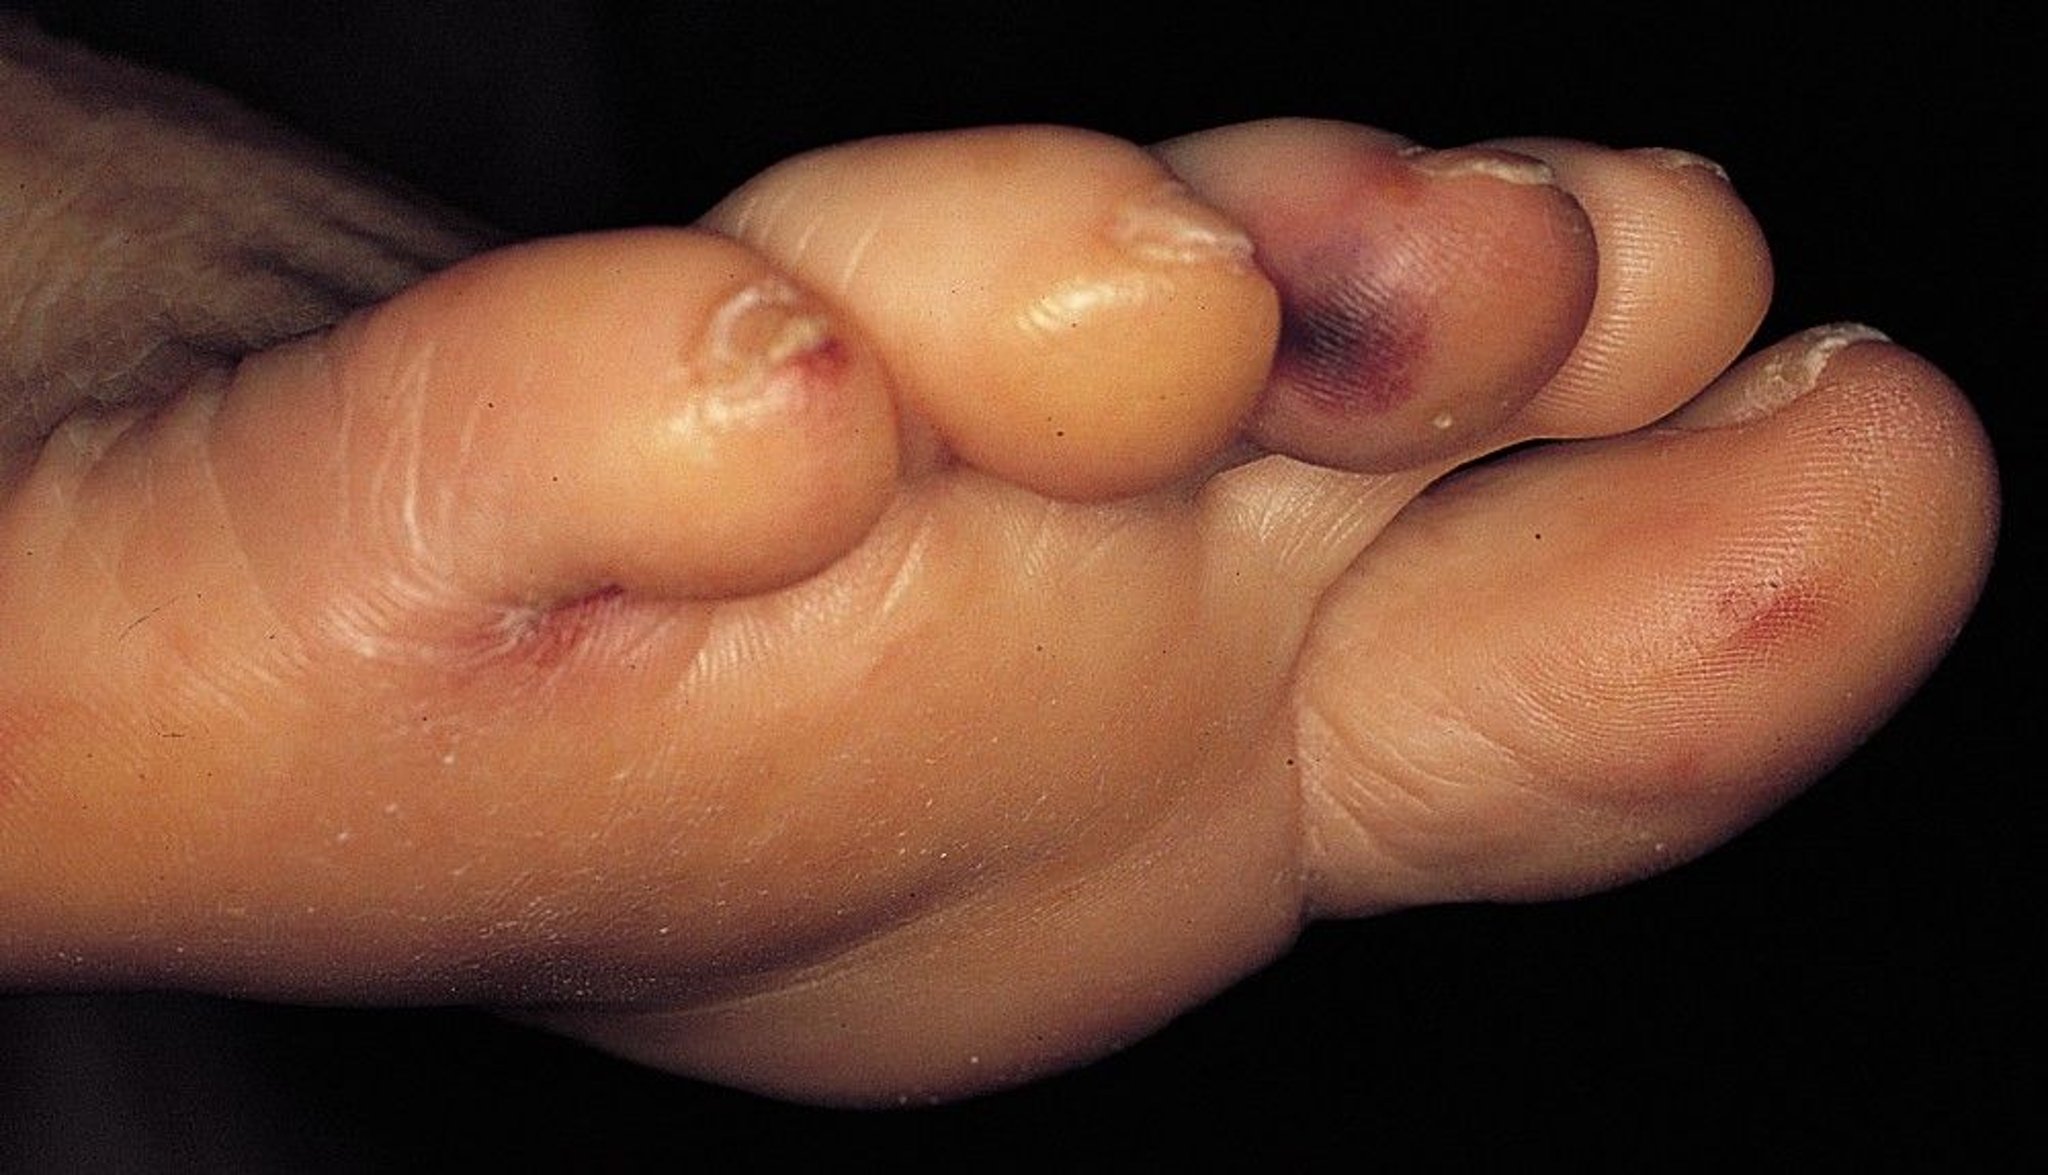

Infective Endocarditis (Osler Nodes)

This patient with infective endocarditis has multiple Osler nodes (tender, erythematous nodules on the toes).